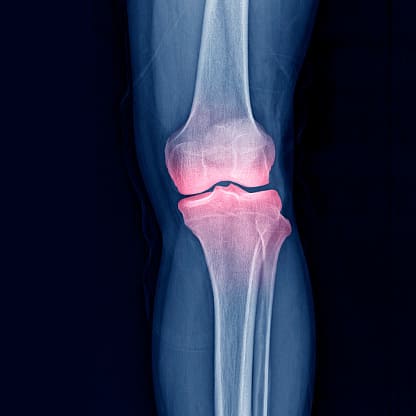

무릎 연골주사 주사 부위 통증과 염증

무릎 연골주사 부작용 중 가장 흔한 것은 주사 부위의 통증과 염증입니다. 주사 시 바늘이 삽입되면서 일시적인 통증이 발생할 수 있으며, 주사 후에는 약물 주입으로 인한 염증 반응이 나타날 수 있습니다. 이러한 무릎 연골주사 부작용은 대개 경미하며, 냉찜질이나 진통제 사용으로 완화될 수 있습니다.

주사 부위의 통증과 염증을 예방하려면 주사 후 일정 시간 동안 무릎을 휴식시키고, 과도한 활동을 피하는 것이 중요합니다. 또한, 주사 부위를 청결하게 유지하여 염증 발생을 최소화할 수 있습니다. 무릎 연골주사 부작용이 심해질 경우, 의료진과 상의하여 적절한 치료를 받는 것이 필요합니다.